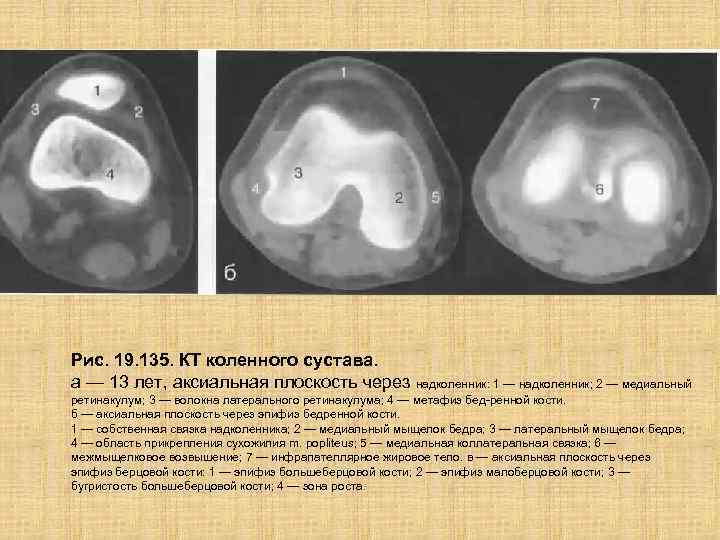

Рис. 19. 135. КТ коленного сустава. а — 13 лет, аксиальная плоскость через надколенник: 1 — надколенник; 2 — медиальный ретинакулум; 3 — волокна латерального ретинакулума; 4 — метафиз бед ренной кости. б — аксиальная плоскость через эпифиз бедренной кости. 1 — собственная связка надколенника; 2 — медиальный мыщелок бедра; 3 — латеральный мыщелок бедра; 4 — область прикрепления сухожилия m. popliteus; 5 — медиальная коллатеральная связка; 6 — межмыщелковое возвышение; 7 — инфрапателлярное жировое тело. в — аксиальная плоскость через эпифиз берцовой кости: 1 — эпифиз большеберцовой кости; 2 — эпифиз малоберцовой кости; 3 — бугристость большеберцовой кости; 4 — зона роста.